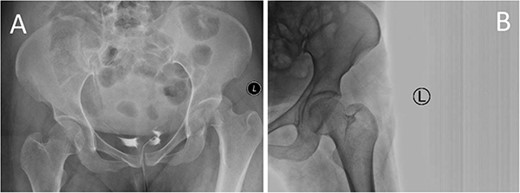

A medically free 42-year female presented to our institute as a life-saving case from a different hospital as she was a victim of unrestrained road traffic accident 2 days prior to presentation. Upon assessment in the emergency department (ER), she was conscious and oriented, and was found to have bilateral lung contusion, and multiple fractures of ribs. She also had a left sided vertical femoral head fracture dislocation comprising around 40% of the femoral head (Fig. 1). Closed reduction under conscious sedation was done in the ER, which was successful based on post-reduction imaging studies (Fig. 2). Her chest injuries were treated with chest tube and observation for 10 days. During that time, discussion was made with the patient regarding her situation and conservative management was chosen by way of bed rest and continuation of skeletal traction for 4 weeks with serial radiographs in the hospital on a weekly basis after clearance of her chest injuries. Skeletal traction was discontinued and she was advised to continue bed to wheelchair mobilization for an additional 2 weeks. After 6-weeks from the injury, a Computed Tomography (CT) was done to the patient and revealed signs of fracture healing (Fig. 3). At 3-years after the injury, she was found to have full painless range of motion of the affected hip and has resumed her activity of daily living without any complaints and the images showed a symmetrical joint space of the hips (Fig. 4).

AP radiographs (A) and frog leg lateral (B) radiographs at 3-year follow-up showing a concentrically reduced hip.